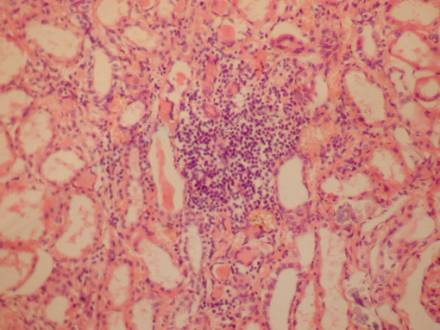

Через 6-12 годин після травми продовжується спостерігатися спостерігається

порушення кровообігу; судини нерівномірного кровонаповненн з лейкостазами та

сепарацією плазми в просвітах окремих судин, виявляються дистрофічні зміни у

епітелії канальців: місцями епітелій набухлий, вакуолізований, в інших ділянках

епітелій глибчастий, спостерігається відсутність ядер епітелію, що відображено

на рисунку 1. Протягом 12-24 годин на фоні вищезазначених змін в стромі дифузно

Рис. 1. Дистрофічні

зміни епітелію канальців. Забарвлення гемотоксилин-еозіном. Х.200.